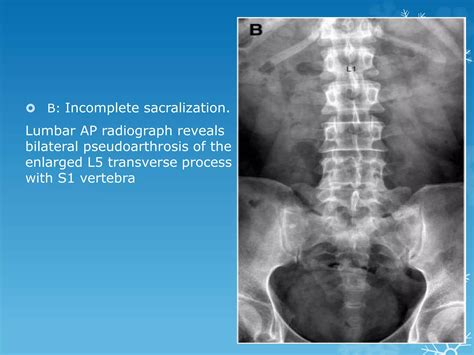

Diagnosing partial sacralization of L5 typically involves a combination of physical examination and imaging tests. Common diagnostic methods include:

• X-rays: To visualize the spine and identify any bony abnormalities.

• partial sacralization of l5 radiology